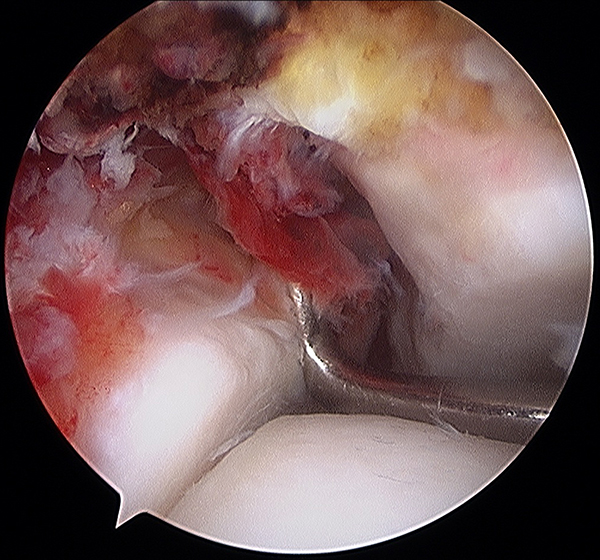

Figura 3: Lesión condral, hallazgo artroscópico.

En 10 casos se diagnosticó patología intra-articular (47,6%), fragmentos osteocondrales en ocho casos y dos pacientes que presentaban fractura del maléolo medial con interposición de tejidos blandos en la fractura. Este último hallazgo, no avalaría la reducción y osteosíntesis percutánea.

La patología intra-articular diagnosticada por artroscopia incluye: cuerpos libres, lesiones osteocondrales, lesiones condrales y lesiones ligamentarias. La incidencia de las lesiones intra-articulares varía según las publicaciones, siendo la patología más frecuente las afecciones del cartílago que oscilan entre 17%-79%13,21,34-40 (tabla 2).

Las lesiones osteocondrales de tibia y astrágalo se diagnostican con Resonancia magnética, pero las lesiones condrales puras pueden no ser detectadas por este medio, por lo que la utilización de la artroscopia como método complementario sería necesario para el diagnóstico agudo de la patología intra-articular para mejorar los resultados clínicos.21